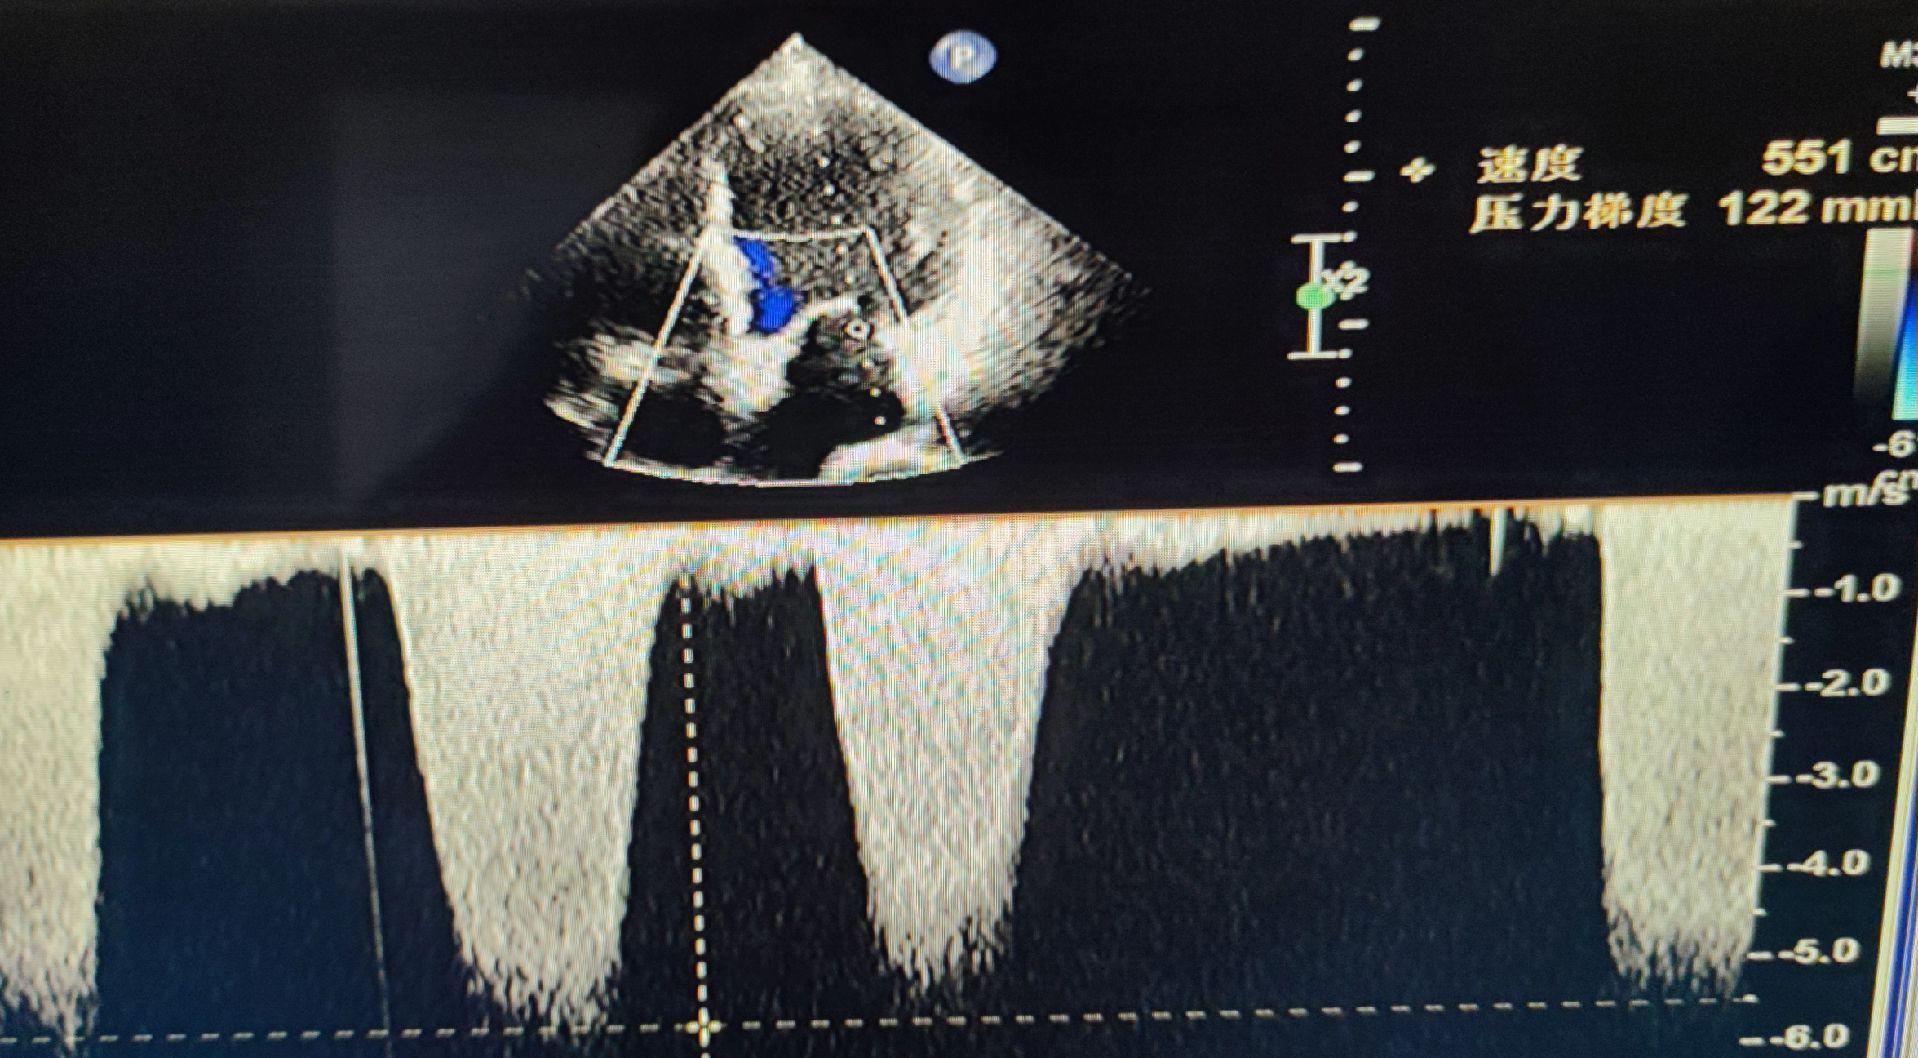

心肌缺血超声改变。室间隔变薄,运动幅度明显减弱 与DSA及心电图对照 DSA前降支远段狭窄99%

梗阻性肥厚型心肌病。家族性者为常染色体显性遗传 女,44岁,体检发现 SAM现象 左室流出道频谱匕首样 已手术